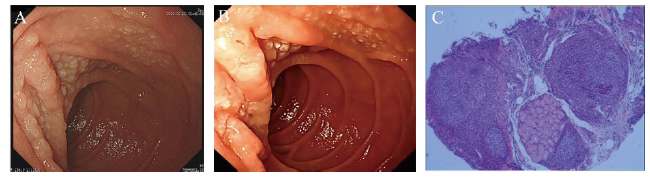

病例3 患者女,42岁,2017年12月6日因“健康体检”就诊于本院,行胃镜检查示十二指肠降部黏膜浅表性改变(图3A),当时未取活检。患者当时主诉无明显不适。2022年3月因“上腹部不适2周”于本院就诊。体格检查无殊。否认高血压、糖尿病、淋巴瘤等病史。总胆固醇>6.40 mmol/L,余实验室检查未见明显异常;胃镜示十二指肠降部见黏膜颗粒状改变(图3B),病灶处病理结果:FL(I级)(图3C);免疫组化标记结果:肿瘤细胞CD20(+),CD10(+),Bcl-2(生发中心+),Bcl-6(+),Ki-67(+,5%~15%),CD21(肿瘤性滤泡边缘+),LMO2(+),CD3(-)。结肠镜显示结肠多发息肉,病理结果示增生性息肉。右侧髂后上棘行骨髓穿刺活检,组织送检结果:流式细胞免疫表型、TCR基因重排、Ig基因重排、骨髓组织学均未见明显异常;PET/CT:全身氟代脱氧葡萄糖代谢未见异常增高;结合HE染色及免疫表型并排除系统性淋巴瘤累及十二指肠,确诊为D-FL(1级)。排除禁忌后于2022年4月起予R2方案化学治疗,具体为:“奥妥珠单抗针1 g,d1,来那度胺5 mg,d1~5”,每次奥妥珠单抗治疗后均有畏寒低热,3 d后可消退。电话随访患者至截稿日,目前化学治疗方案同前,主诉有时感上腹部不适,伴夜间盗汗,感乏力,其余无明显不适。

图3 病例3 D-FL患者胃镜及病理图片

注:A、B分别为2017年12月、2022年3月胃镜下十二指肠降部黏膜表现;C为2022年3月十二指肠降部黏膜病理(HE染色,40)。